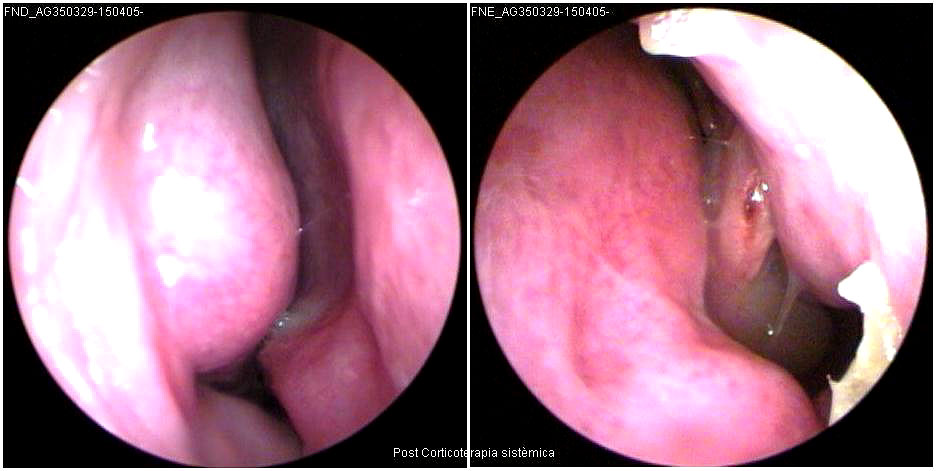

JFC Edema de Reincke